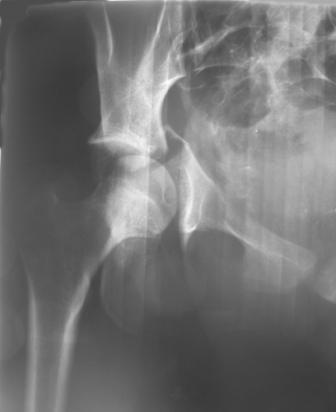

30/11/04 |  30/11/04 |  30/11/04 |  14/12/04 |  14/12/04 |  14/02/05 |  14/02/05 |  21/02/05 | Уважаемые коллеги! Случилось вторичное смещение вертлужной впадины после операции. Посоветуйте, что делать. Пациентка 18 лет. Травма 19.11.04. D.s.: Закрытыый Т-образный высокий перелом правой вертлужной впадины. Закрытый перелом м\мыщелкового возвышения левой б\берцовой кости. 9.12.04 операция - открытая репозиция, остеосинтез переломам вертлужной впадины. 30.12.05 выписаны на амбулаторное лечение с рекомендациями не вставать на правую ногу. 14.02.05 при контрольном осмотре на Р-граммах выявлено вторичное смещение передней колонны. Клинически подвывиха нет, имеется умеренная приводящая контрактура правого тазобедренного сустава, гипотрофия мышц н\конечностей. Госпитализирована в травмотделение. Выполнено КТ. Имеется смещение передней колонны кнутриЮ диастаз 8 мм. Посоветуйте пожалуйста, что предпринять в данной ситуации.

АС> этих повреждениях. Разгрузка сустава до 5 мес. А деформирующий артроз в

Сустав-то как раз неплох, поскольку впадина почти вся конгруэнтна, по крайней мере вся нагружаемая часть, и подвывиха бедра нет. Артроз в перспективе тут, конечно, не исключить, но на первом плане проблема целости тазового кольца, т.е. нестабильное несращение, о чем А. Рунков писал. На седалищной дефект, и если и разошедшееся основание лонной не срастется, то болезненные проявления могут быть сразу после начала нагрузки, как ее не отсрочивай.